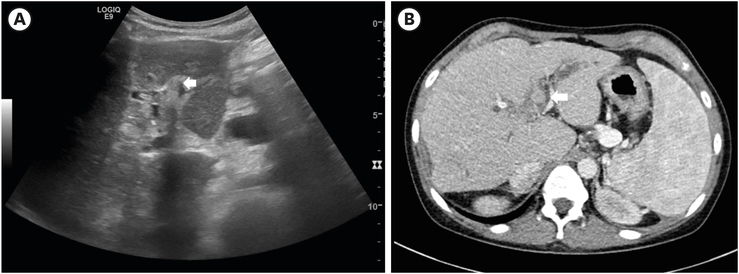

She was admitted to the pediatric department for conservative management of cholangitis and ileus. Liver ultrasonography was done on the 2nd day of admission. It revealed acute on chronic cholangiohepatitis. Echogenic material with posterior shadowing at portoenterostomy site was found in liver ultrasonography at two months prior to the ED visit. This finding was substituted by echogenic fluid at the same site (Fig. 1A). Abdominal computed tomography (CT) taken around the same time revealed stone-like material at the same location (Fig. 1B). Intravenous teicoplanin and meropenem were applied. They were also used in the previous event. However, on hospital day 9, she started to complain more severe abdominal pain. Gaseous distension in the X-ray did not improve. It seemed to be exacerbating (Fig. 2A). Abdominal CT was taken on hospital day 12. It showed long segmental dilatation of the small bowel with obstruction with a dense material that was about 3.1×3.9 cm size in the ileum. Distally migrated biliary stone was suspected for the dense material (Fig. 2B).

Fig. 1

Stone-like material in the portoenterostomy site (A) in liver ultrasonography and (B) in computed tomogram found at 2 months before visiting emergency room (arrow).